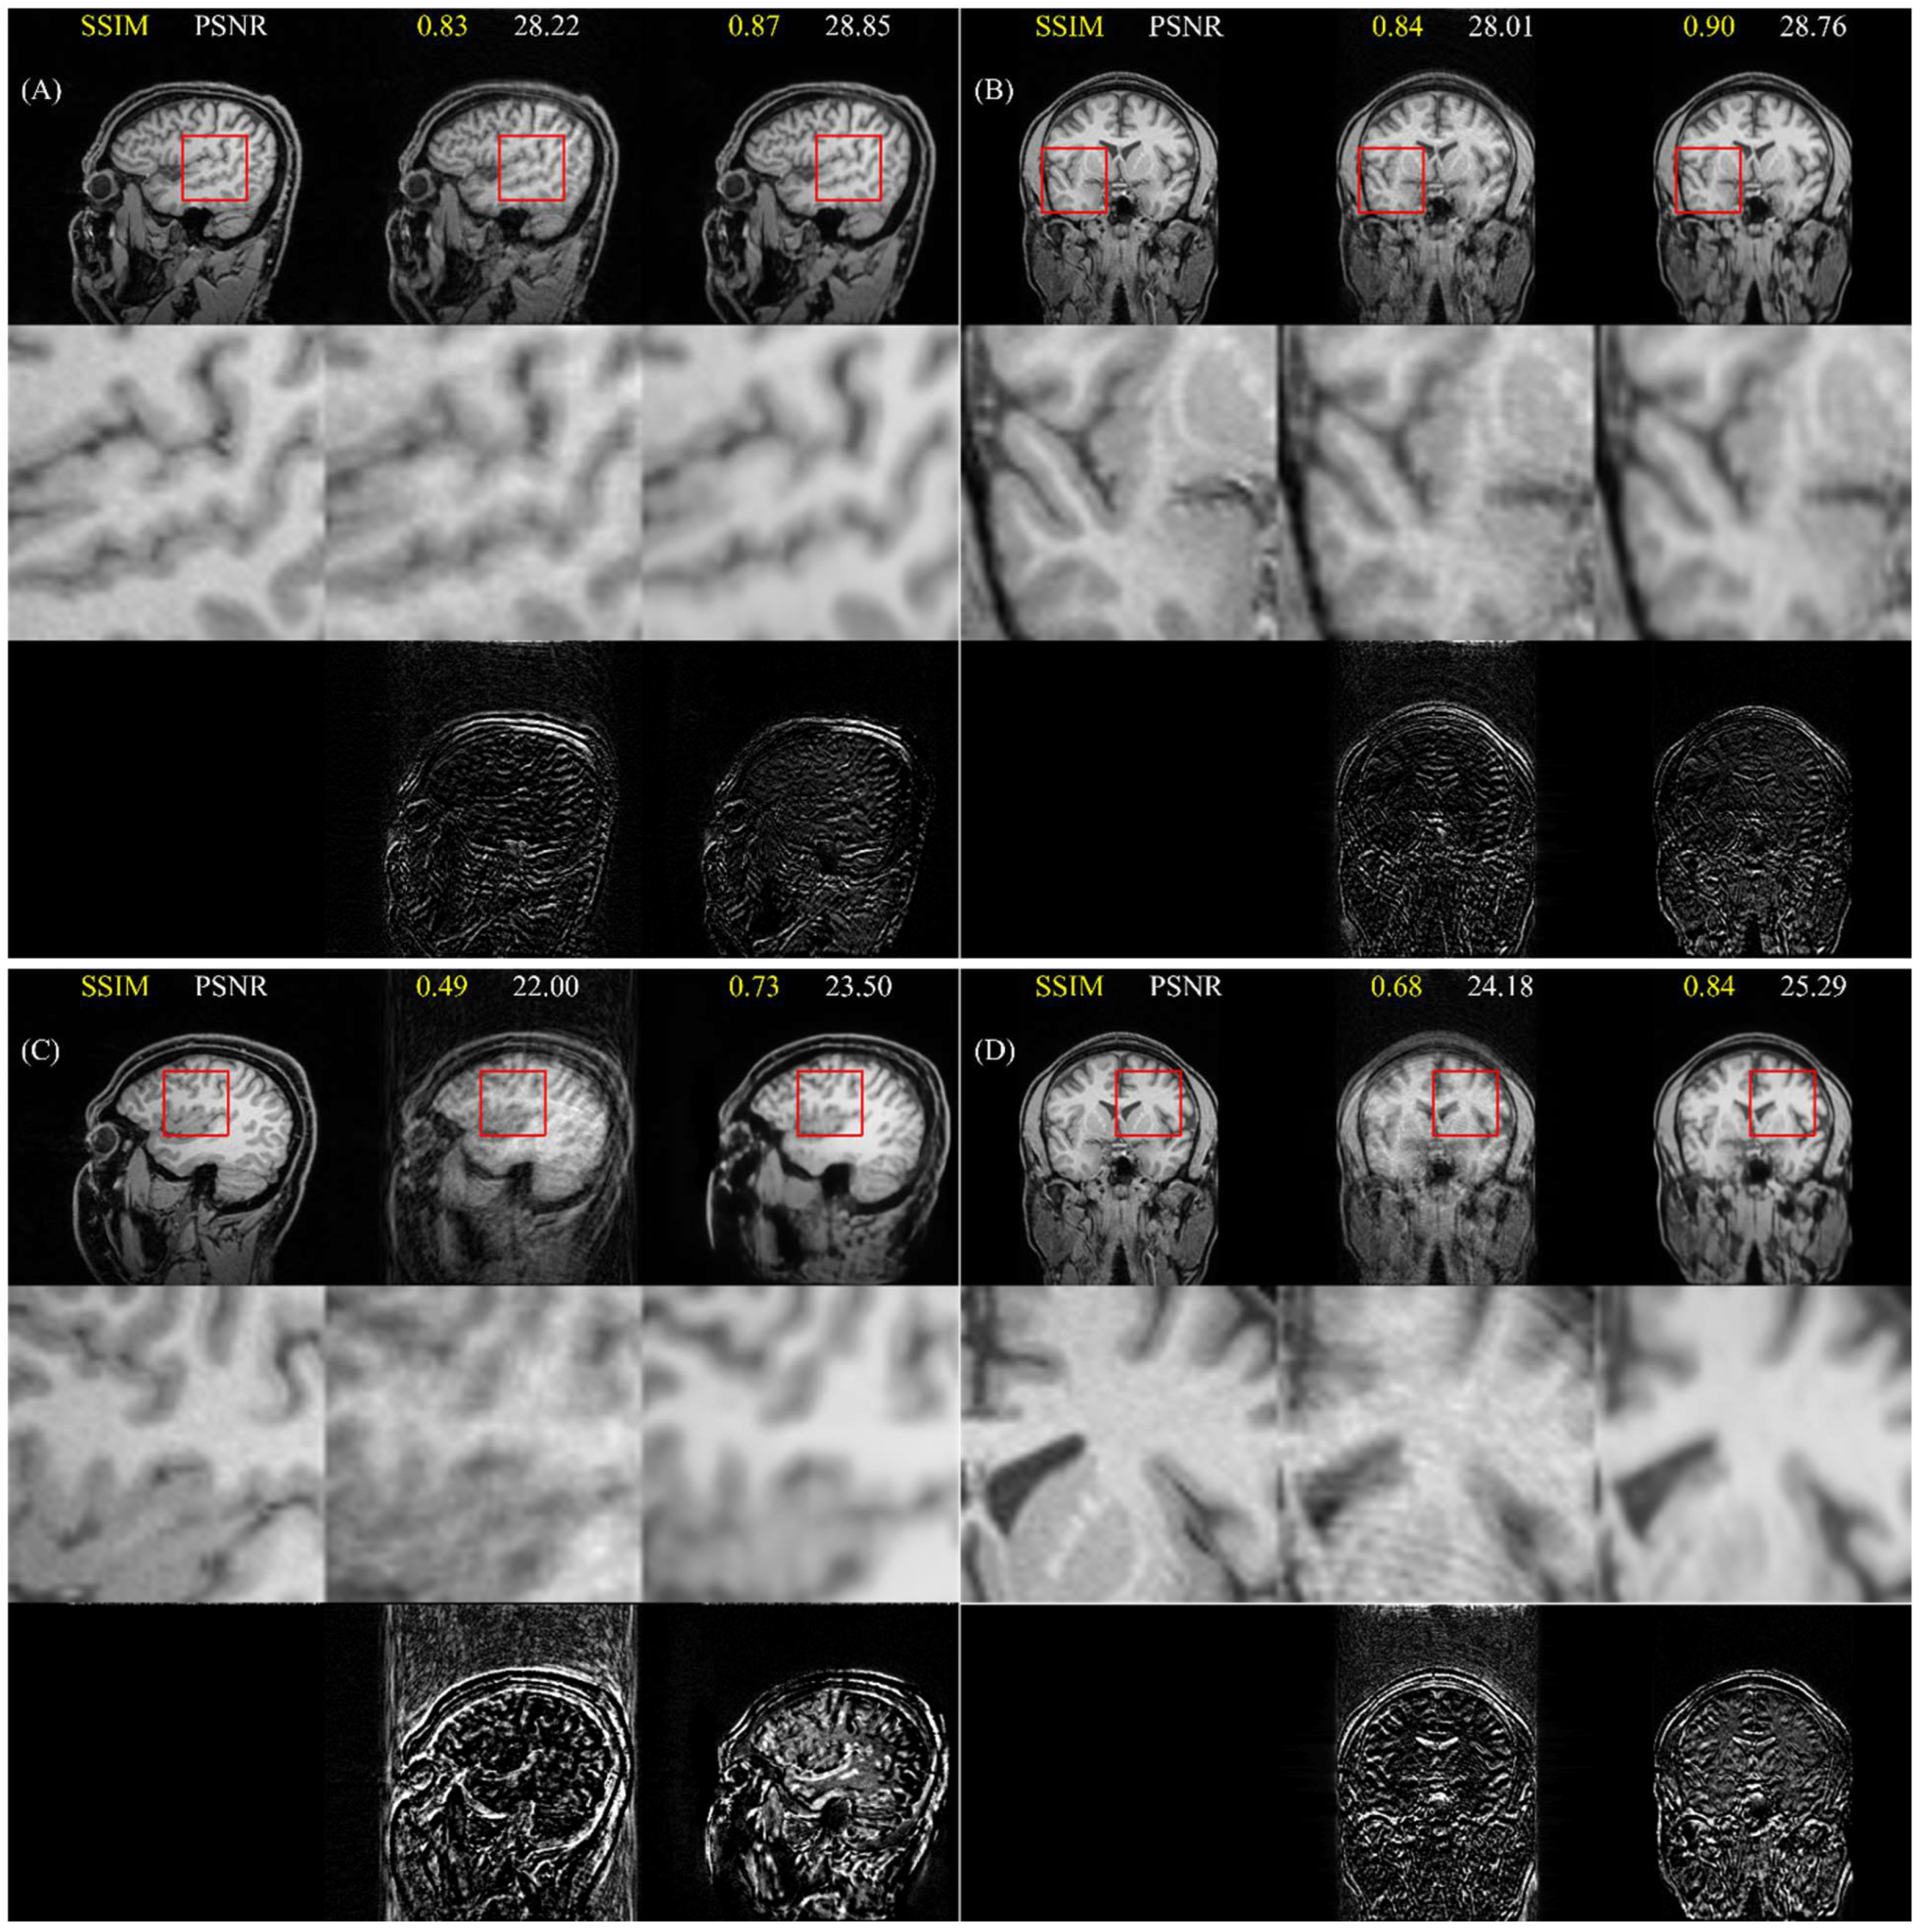

4.4. Cross-Dataset Generalization

5.4. Cross-Dataset Generalization